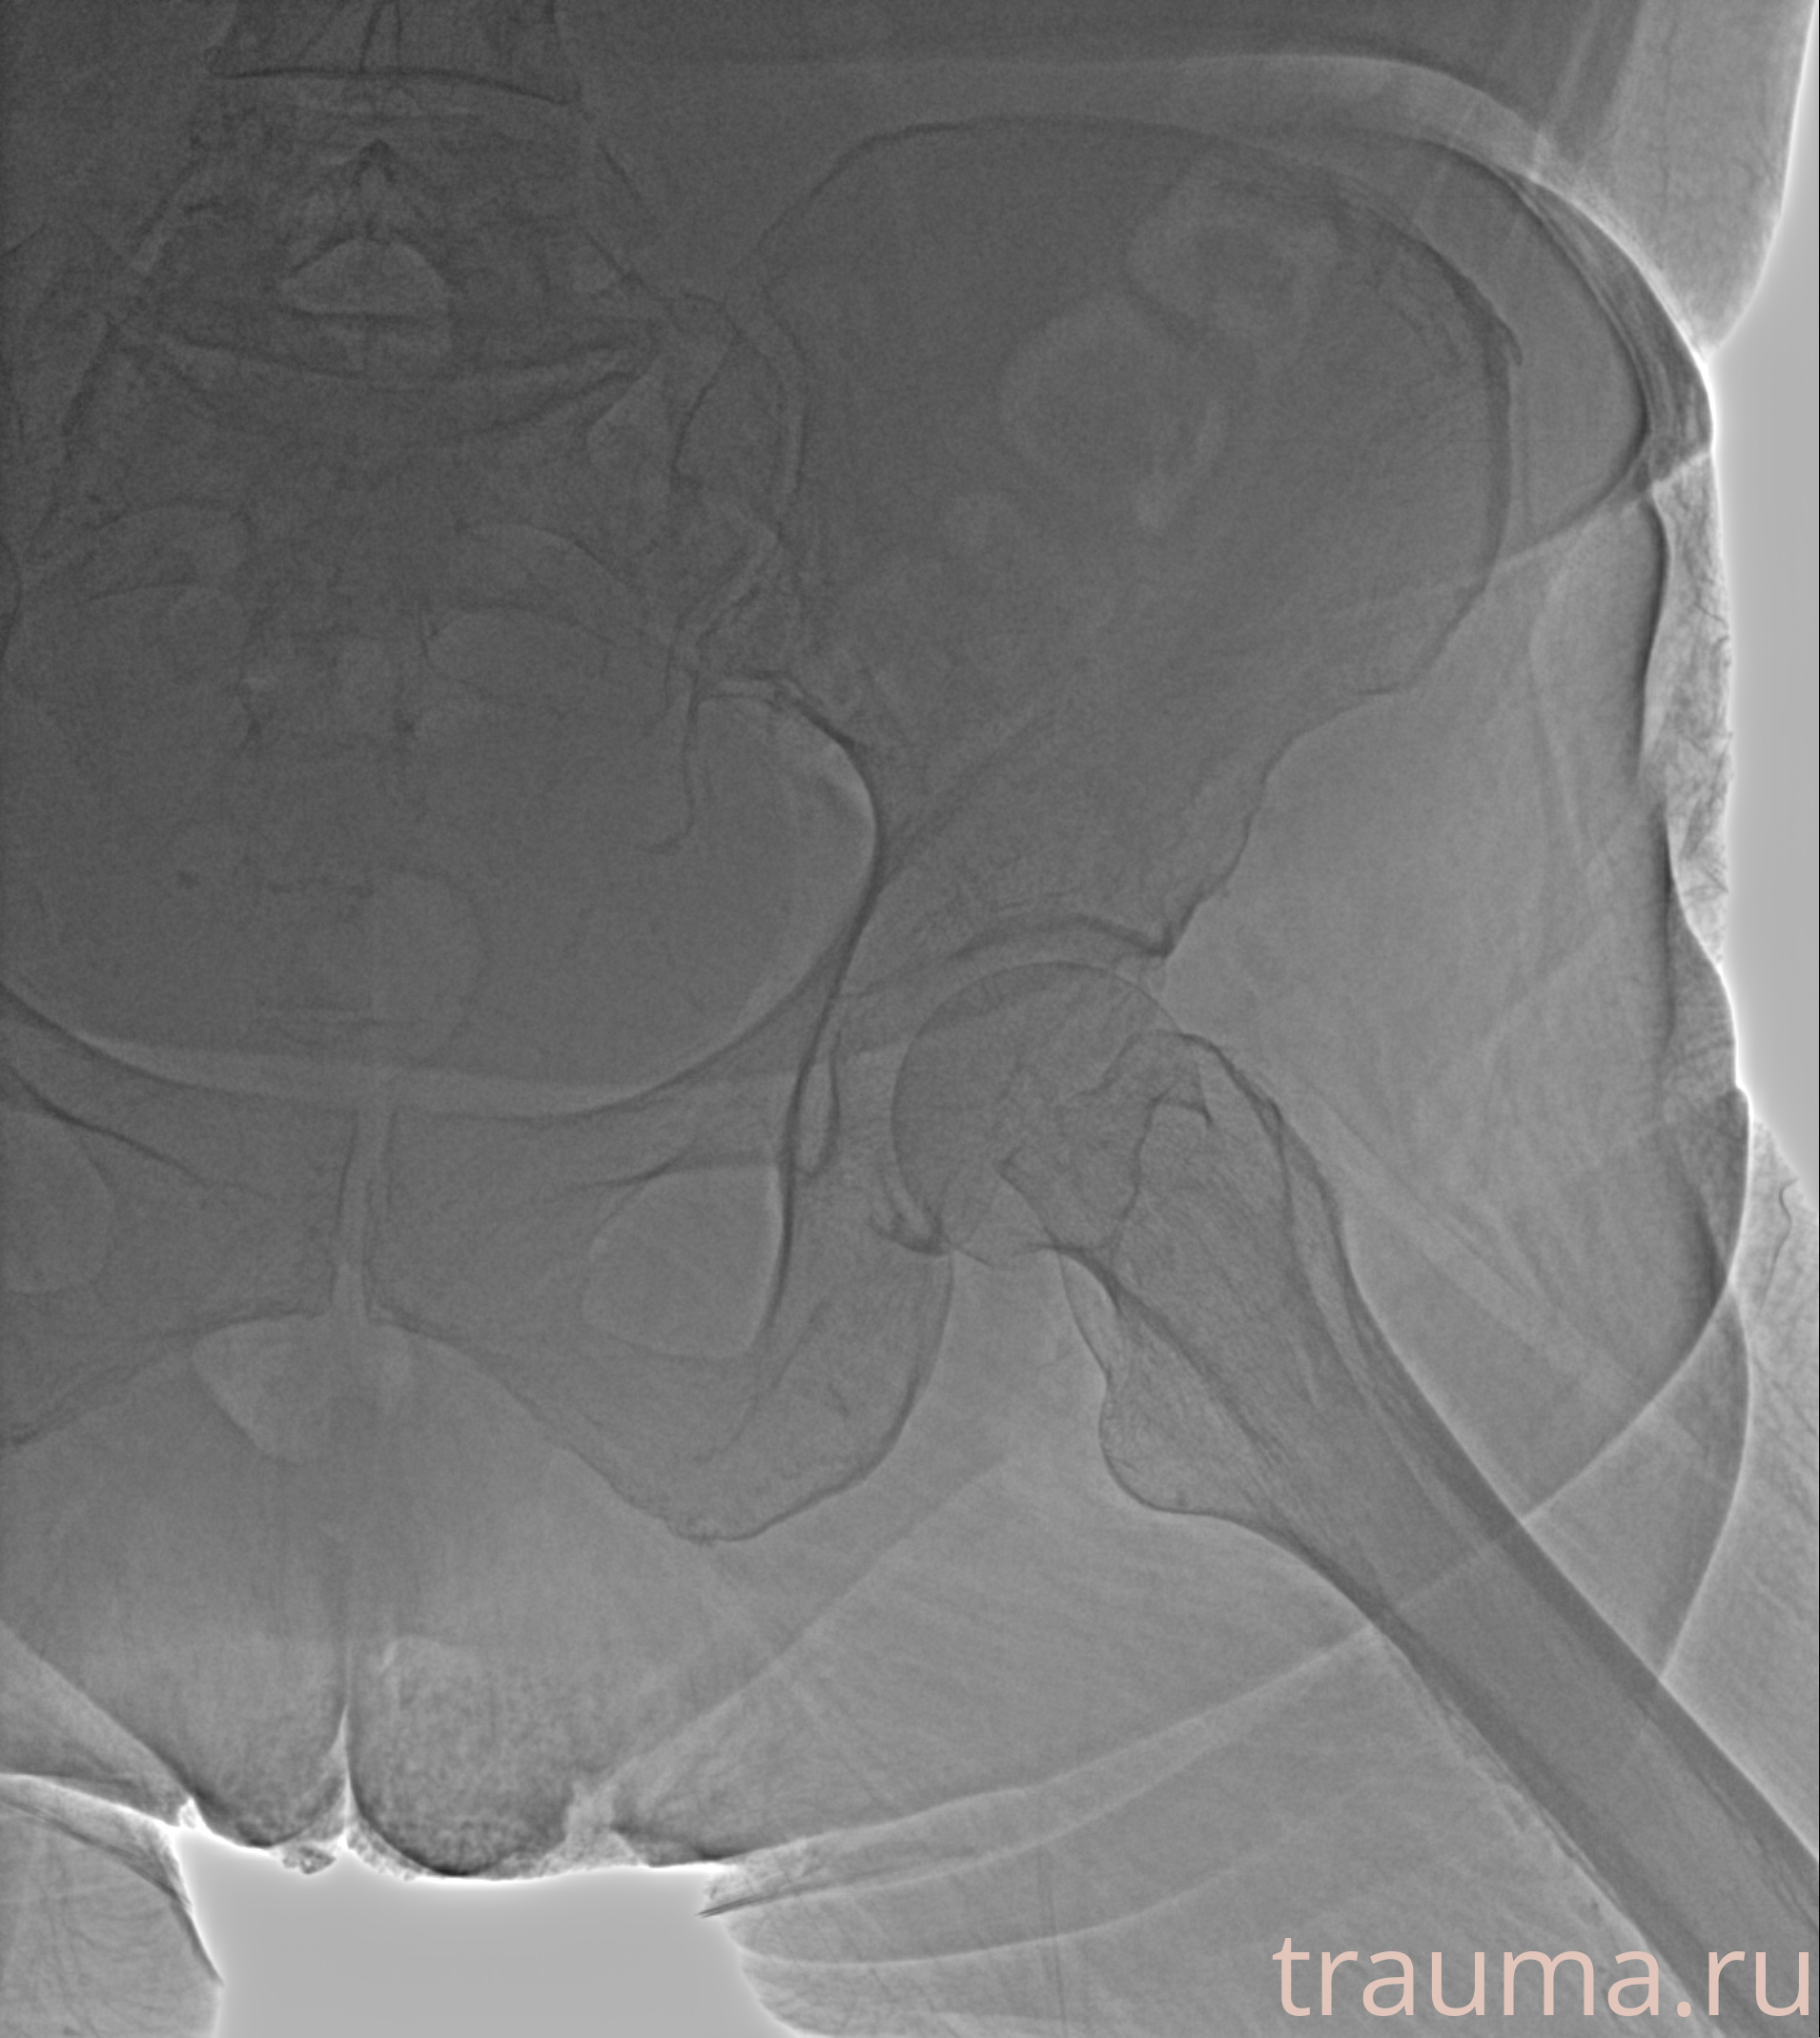

Рентгенограммы

Рентген на дому: по вашему адресу приезжает врач-рентгенолог, травматолог-ортопед с мобильным рентгеновским аппаратом, проводит диагностику травмы или заболевания, делает необходимые рентгенограммы, дает рекомендации по дальнейшему лечению. Получить качественные снимки в домашних условиях возможно благодаря уникальной методике, разработанной МосРентген Центром для института  Склифосовского